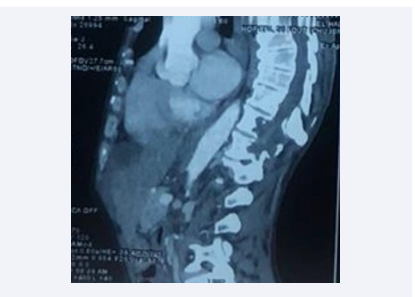

Diagnosis of paravertebral hydatid cysts is generally based on medical imaging, mainly computed tomography (CT) or magnetic resonance imaging (MRI). The latter is the most effective examination for visualizing the cyst, determining its size and exact topography, and studying lesion relationships with nerve structures and the meninges [6]. Certain MRI signs are pathognomonic of echinococcosis, such as the hypointense nature of the cystic wall on T1- and T2-weighted sequences [9] (Figure 3).

Sagittal section of spinal cord MRI showing multiple  vertebral and paravertebral cystic formations at D9, D10 and D11  with endocanal extension.

Figure 3: Sagittal section of spinal cord MRI showing multiple vertebral and paravertebral cystic formations at D9, D10 and D11 with endocanal extension.